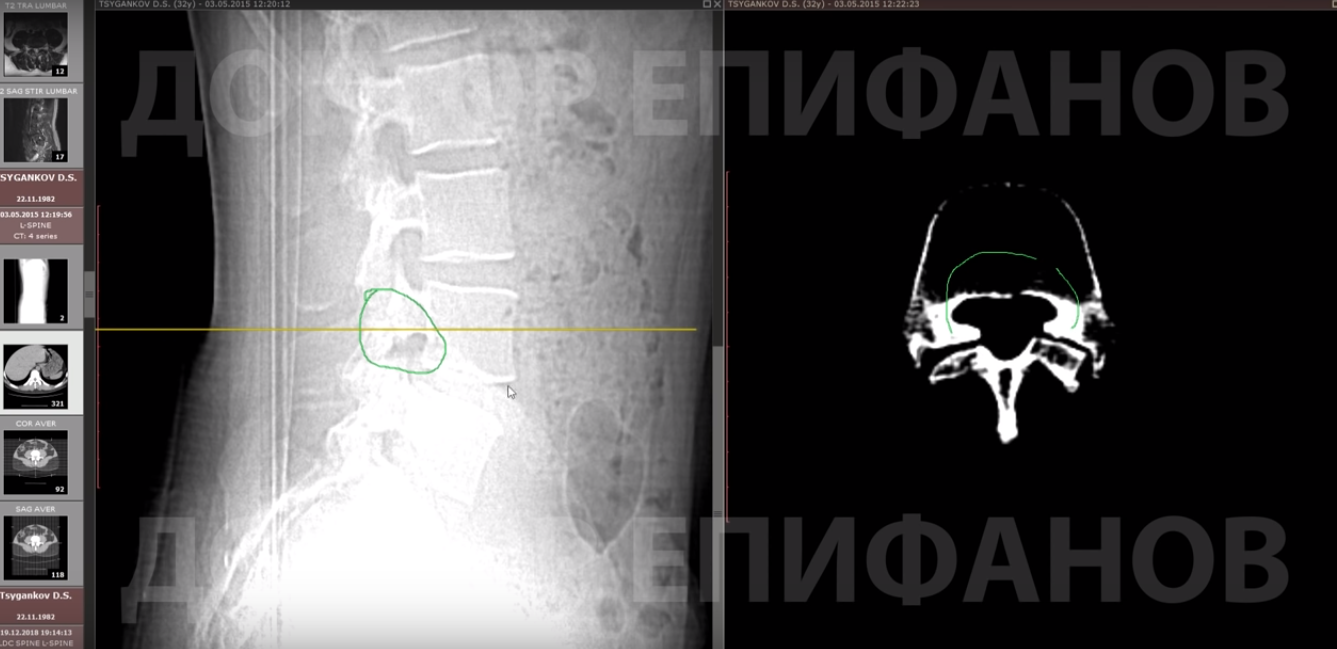

На снимках виден дисбаланс в этом сегменте: позвонок уехал вперёд примерно на 5-6 мм, есть незаращение душки кольца позвонка.

В отростках, которые скрепляют позвонок, видна щель. Значит, он не зафиксирован, его можно рассматривать как отдельную составляющую.

А теперь смотрим тот позвонок, который сместился вперед. Почему это произошло? Потому что есть разрыв и потом идет продолжение отростка.

Дыра между ними — и есть причина боли. Позвонок стремится уехать вперёд, его держит только диск. И этот диск постепенно теряет высоту, становится слабым, чёрным, дистрофируется — слишком высокая на него нагрузка.

Теперь мы посмотрим 3D КТ (мультиспиральная компьютерная томография) интересующего сегмента. Каждый позвонок имеет замкнутое кольцо. Кольцо интересующего нас позвонка не замкнуто. Мы можем увидеть, что оно разорвано.